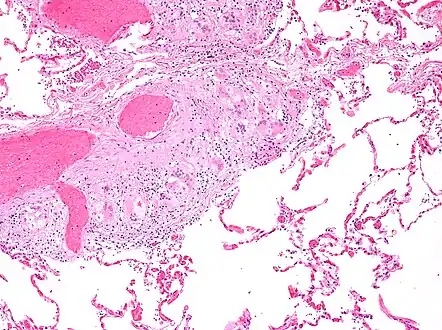

Two asteroid bodies. H&E stain.

An asteroid body is a microscopic finding seen within the giant cells of granulomas in diseases such as sarcoidosis and foreign-body giant cell reactions.[1]